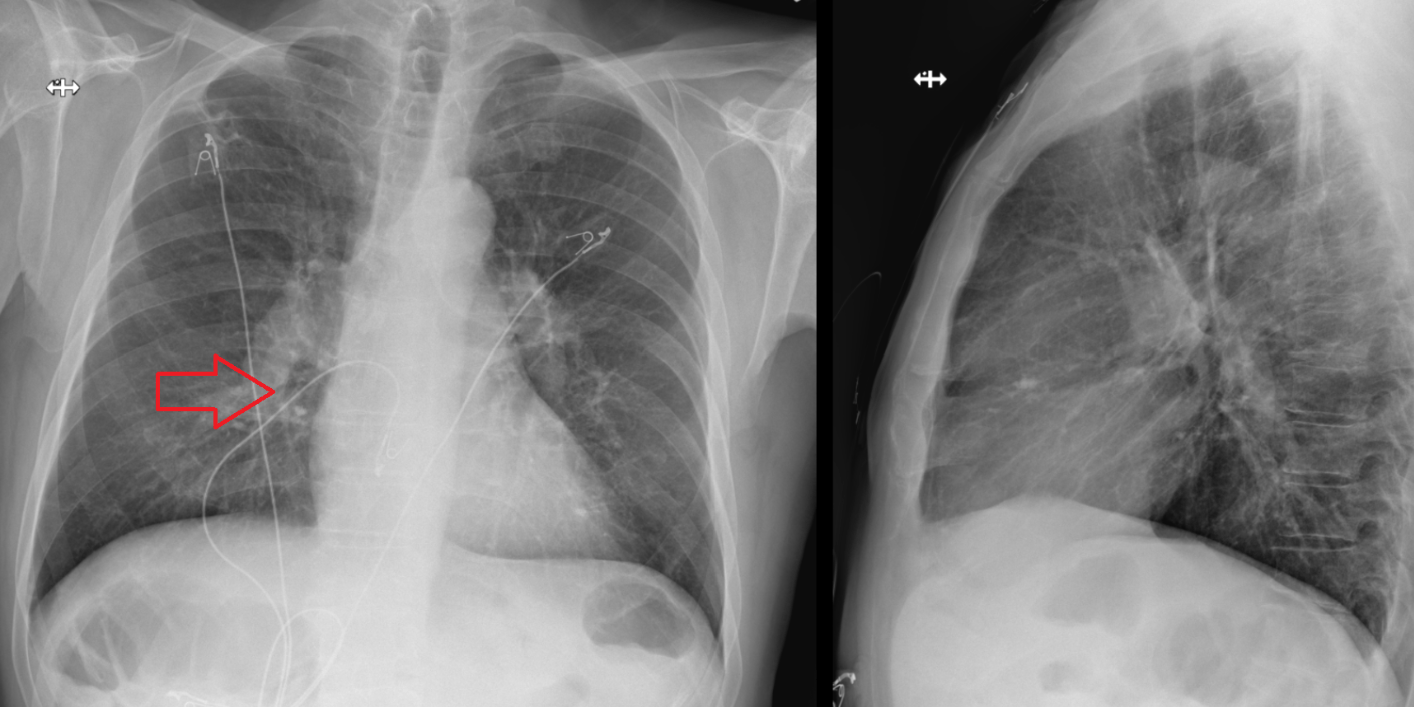

Name this condition.

What is pulmonary artery hypertension or CTEPH?